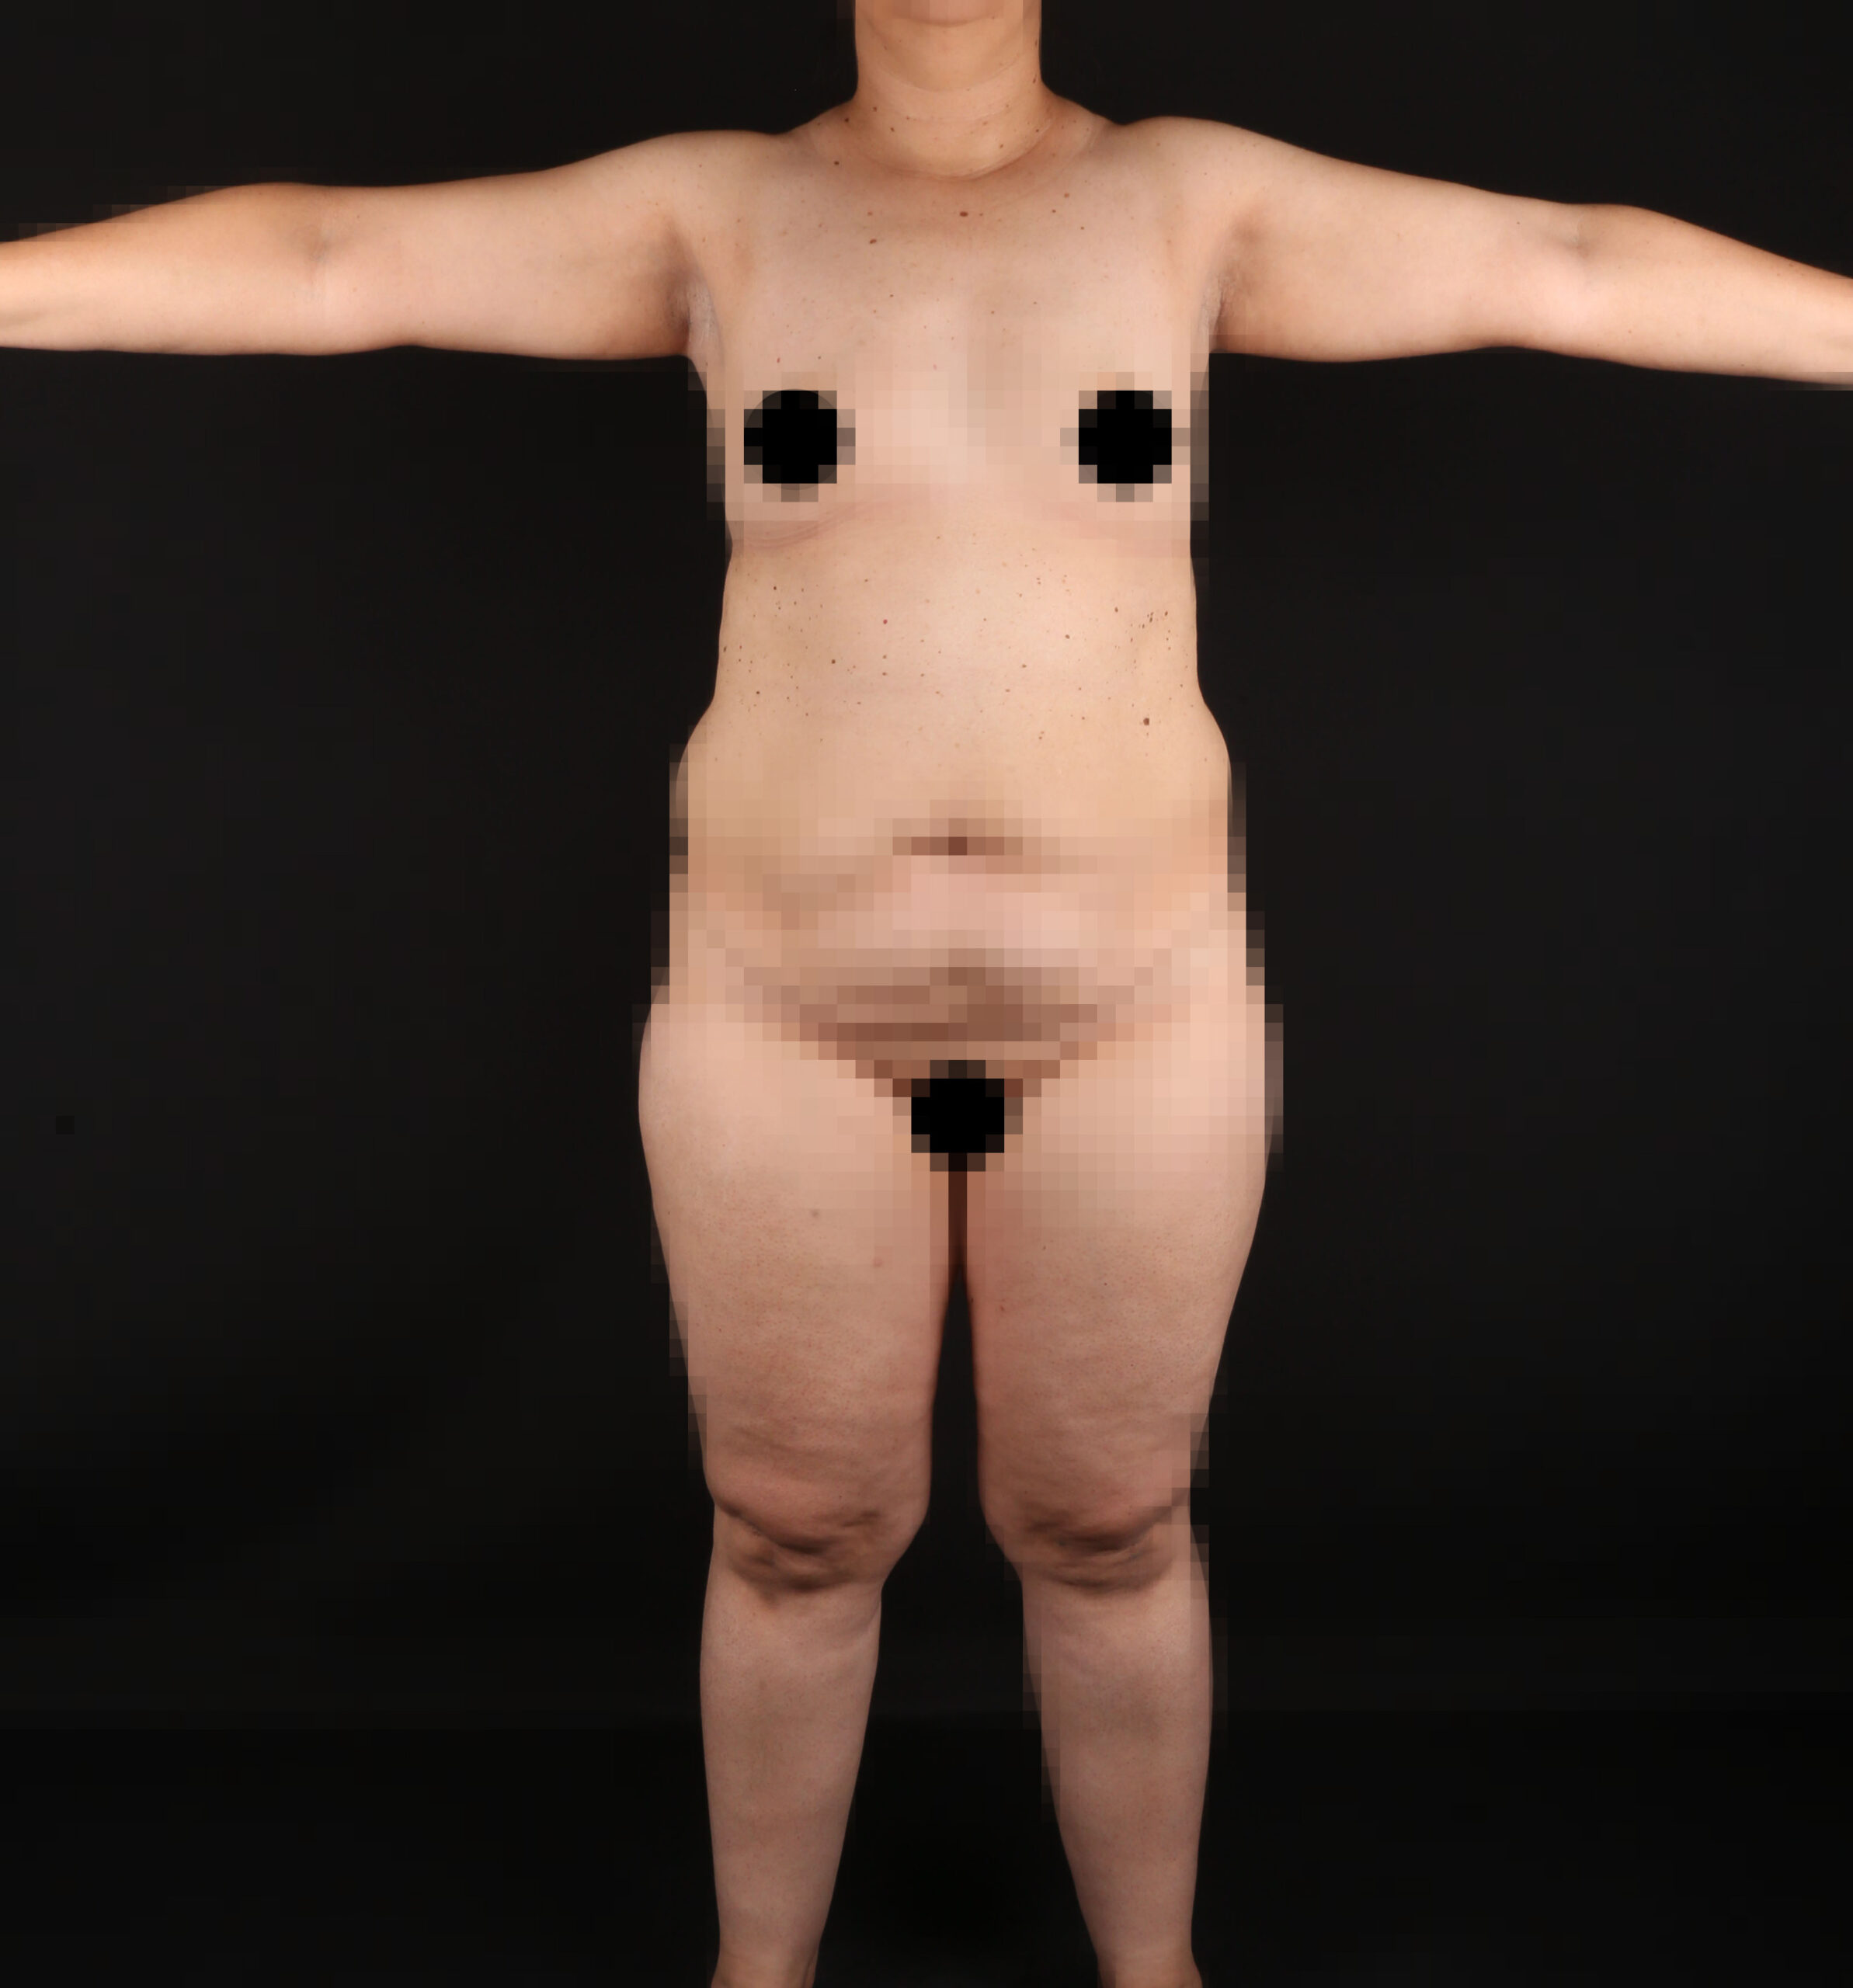

Es una ayuda diagnóstica complementaria que se utiliza para capturar imágenes de cualquier parte del cuerpo, aplicando técnicas que permitan obtener fotografías proporcionales, detalladas y nítidas; empleadas para medir, trazar, predeterminar y planear un proceso quirúrgico.

Es utilizada para crear imágenes del cuerpo humano, o partes de él, con propósitos clínicos que buscan revelar, diagnosticar y planear un tratamiento médico.